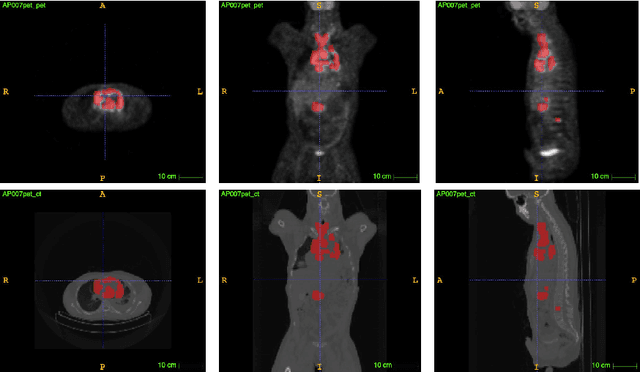

Abstract:Single-modality medical images generally do not contain enough information to reach an accurate and reliable diagnosis. For this reason, physicians generally diagnose diseases based on multimodal medical images such as, e.g., PET/CT. The effective fusion of multimodal information is essential to reach a reliable decision and explain how the decision is made as well. In this paper, we propose a fusion framework for multimodal medical image segmentation based on deep learning and the Dempster-Shafer theory of evidence. In this framework, the reliability of each single modality image when segmenting different objects is taken into account by a contextual discounting operation. The discounted pieces of evidence from each modality are then combined by Dempster's rule to reach a final decision. Experimental results with a PET-CT dataset with lymphomas and a multi-MRI dataset with brain tumors show that our method outperforms the state-of-the-art methods in accuracy and reliability.

Abstract:An automatic evidential segmentation method based on Dempster-Shafer theory and deep learning is proposed to segment lymphomas from three-dimensional Positron Emission Tomography (PET) and Computed Tomography (CT) images. The architecture is composed of a deep feature-extraction module and an evidential layer. The feature extraction module uses an encoder-decoder framework to extract semantic feature vectors from 3D inputs. The evidential layer then uses prototypes in the feature space to compute a belief function at each voxel quantifying the uncertainty about the presence or absence of a lymphoma at this location. Two evidential layers are compared, based on different ways of using distances to prototypes for computing mass functions. The whole model is trained end-to-end by minimizing the Dice loss function. The proposed combination of deep feature extraction and evidential segmentation is shown to outperform the baseline UNet model as well as three other state-of-the-art models on a dataset of 173 patients.

Abstract:Lymphoma detection and segmentation from whole-body Positron Emission Tomography/Computed Tomography (PET/CT) volumes are crucial for surgical indication and radiotherapy. Designing automatic segmentation methods capable of effectively exploiting the information from PET and CT as well as resolving their uncertainty remain a challenge. In this paper, we propose an lymphoma segmentation model using an UNet with an evidential PET/CT fusion layer. Single-modality volumes are trained separately to get initial segmentation maps and an evidential fusion layer is proposed to fuse the two pieces of evidence using Dempster-Shafer theory (DST). Moreover, a multi-task loss function is proposed: in addition to the use of the Dice loss for PET and CT segmentation, a loss function based on the concordance between the two segmentation is added to constrain the final segmentation. We evaluate our proposal on a database of polycentric PET/CT volumes of patients treated for lymphoma, delineated by the experts. Our method get accurate segmentation results with Dice score of 0.726, without any user interaction. Quantitative results show that our method is superior to the state-of-the-art methods.

Abstract:PET and CT are two modalities widely used in medical image analysis. Accurately detecting and segmenting lymphomas from these two imaging modalities are critical tasks for cancer staging and radiotherapy planning. However, this task is still challenging due to the complexity of PET/CT images, and the computation cost to process 3D data. In this paper, a segmentation method based on belief functions is proposed to segment lymphomas in 3D PET/CT images. The architecture is composed of a feature extraction module and an evidential segmentation (ES) module. The ES module outputs not only segmentation results (binary maps indicating the presence or absence of lymphoma in each voxel) but also uncertainty maps quantifying the classification uncertainty. The whole model is optimized by minimizing Dice and uncertainty loss functions to increase segmentation accuracy. The method was evaluated on a database of 173 patients with diffuse large b-cell lymphoma. Quantitative and qualitative results show that our method outperforms the state-of-the-art methods.